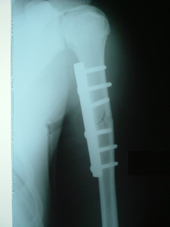

| Fracture Humerus |

Fracture humerus post op |